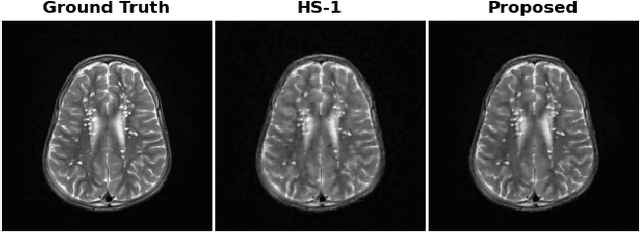

Abstract:Total Variation regularization (TV) is a seminal approach for image recovery. TV involves the norm of the image's gradient, aggregated over all pixel locations. Therefore, TV leads to piece-wise constant solutions, resulting in what is known as the "staircase effect." To mitigate this effect, the Hessian Schatten norm regularization (HSN) employs second-order derivatives, represented by the pth norm of eigenvalues in the image hessian, summed across all pixels. HSN demonstrates superior structure-preserving properties compared to TV. However, HSN solutions tend to be overly smoothed. To address this, we introduce a non-convex shrinkage penalty applied to the Hessian's eigenvalues, deviating from the convex lp norm. It is important to note that the shrinkage penalty is not defined directly in closed form, but specified indirectly through its proximal operation. This makes constructing a provably convergent algorithm difficult as the singular values are also defined through a non-linear operation. However, we were able to derive a provably convergent algorithm using proximal operations. We prove the convergence by establishing that the proposed regularization adheres to restricted proximal regularity. The images recovered by this regularization were sharper than the convex counterparts.

Abstract:Regularization plays a crucial role in reliably utilizing imaging systems for scientific and medical investigations. It helps to stabilize the process of computationally undoing any degradation caused by physical limitations of the imaging process. In the past decades, total variation regularization, especially second-order total variation (TV-2) regularization played a dominant role in the literature. Two forms of generalizations, namely Hessian-Schatten norm (HSN) regularization, and total generalized variation (TGV) regularization, have been recently proposed and have become significant developments in the area of regularization for imaging inverse problems owing to their performance. Here, we develop a novel regularization for image recovery that combines the strengths of these well-known forms. We achieve this by restricting the maximization space in the dual form of HSN in the same way that TGV is obtained from TV-2. We name the new regularization as the generalized Hessian-Schatten norm regularization (GHSN), and we develop a novel optimization method for image reconstruction using the new form of regularization based on the well-known framework called alternating direction method of multipliers (ADMM). We demonstrate the strength of the GHSN using some reconstruction examples.